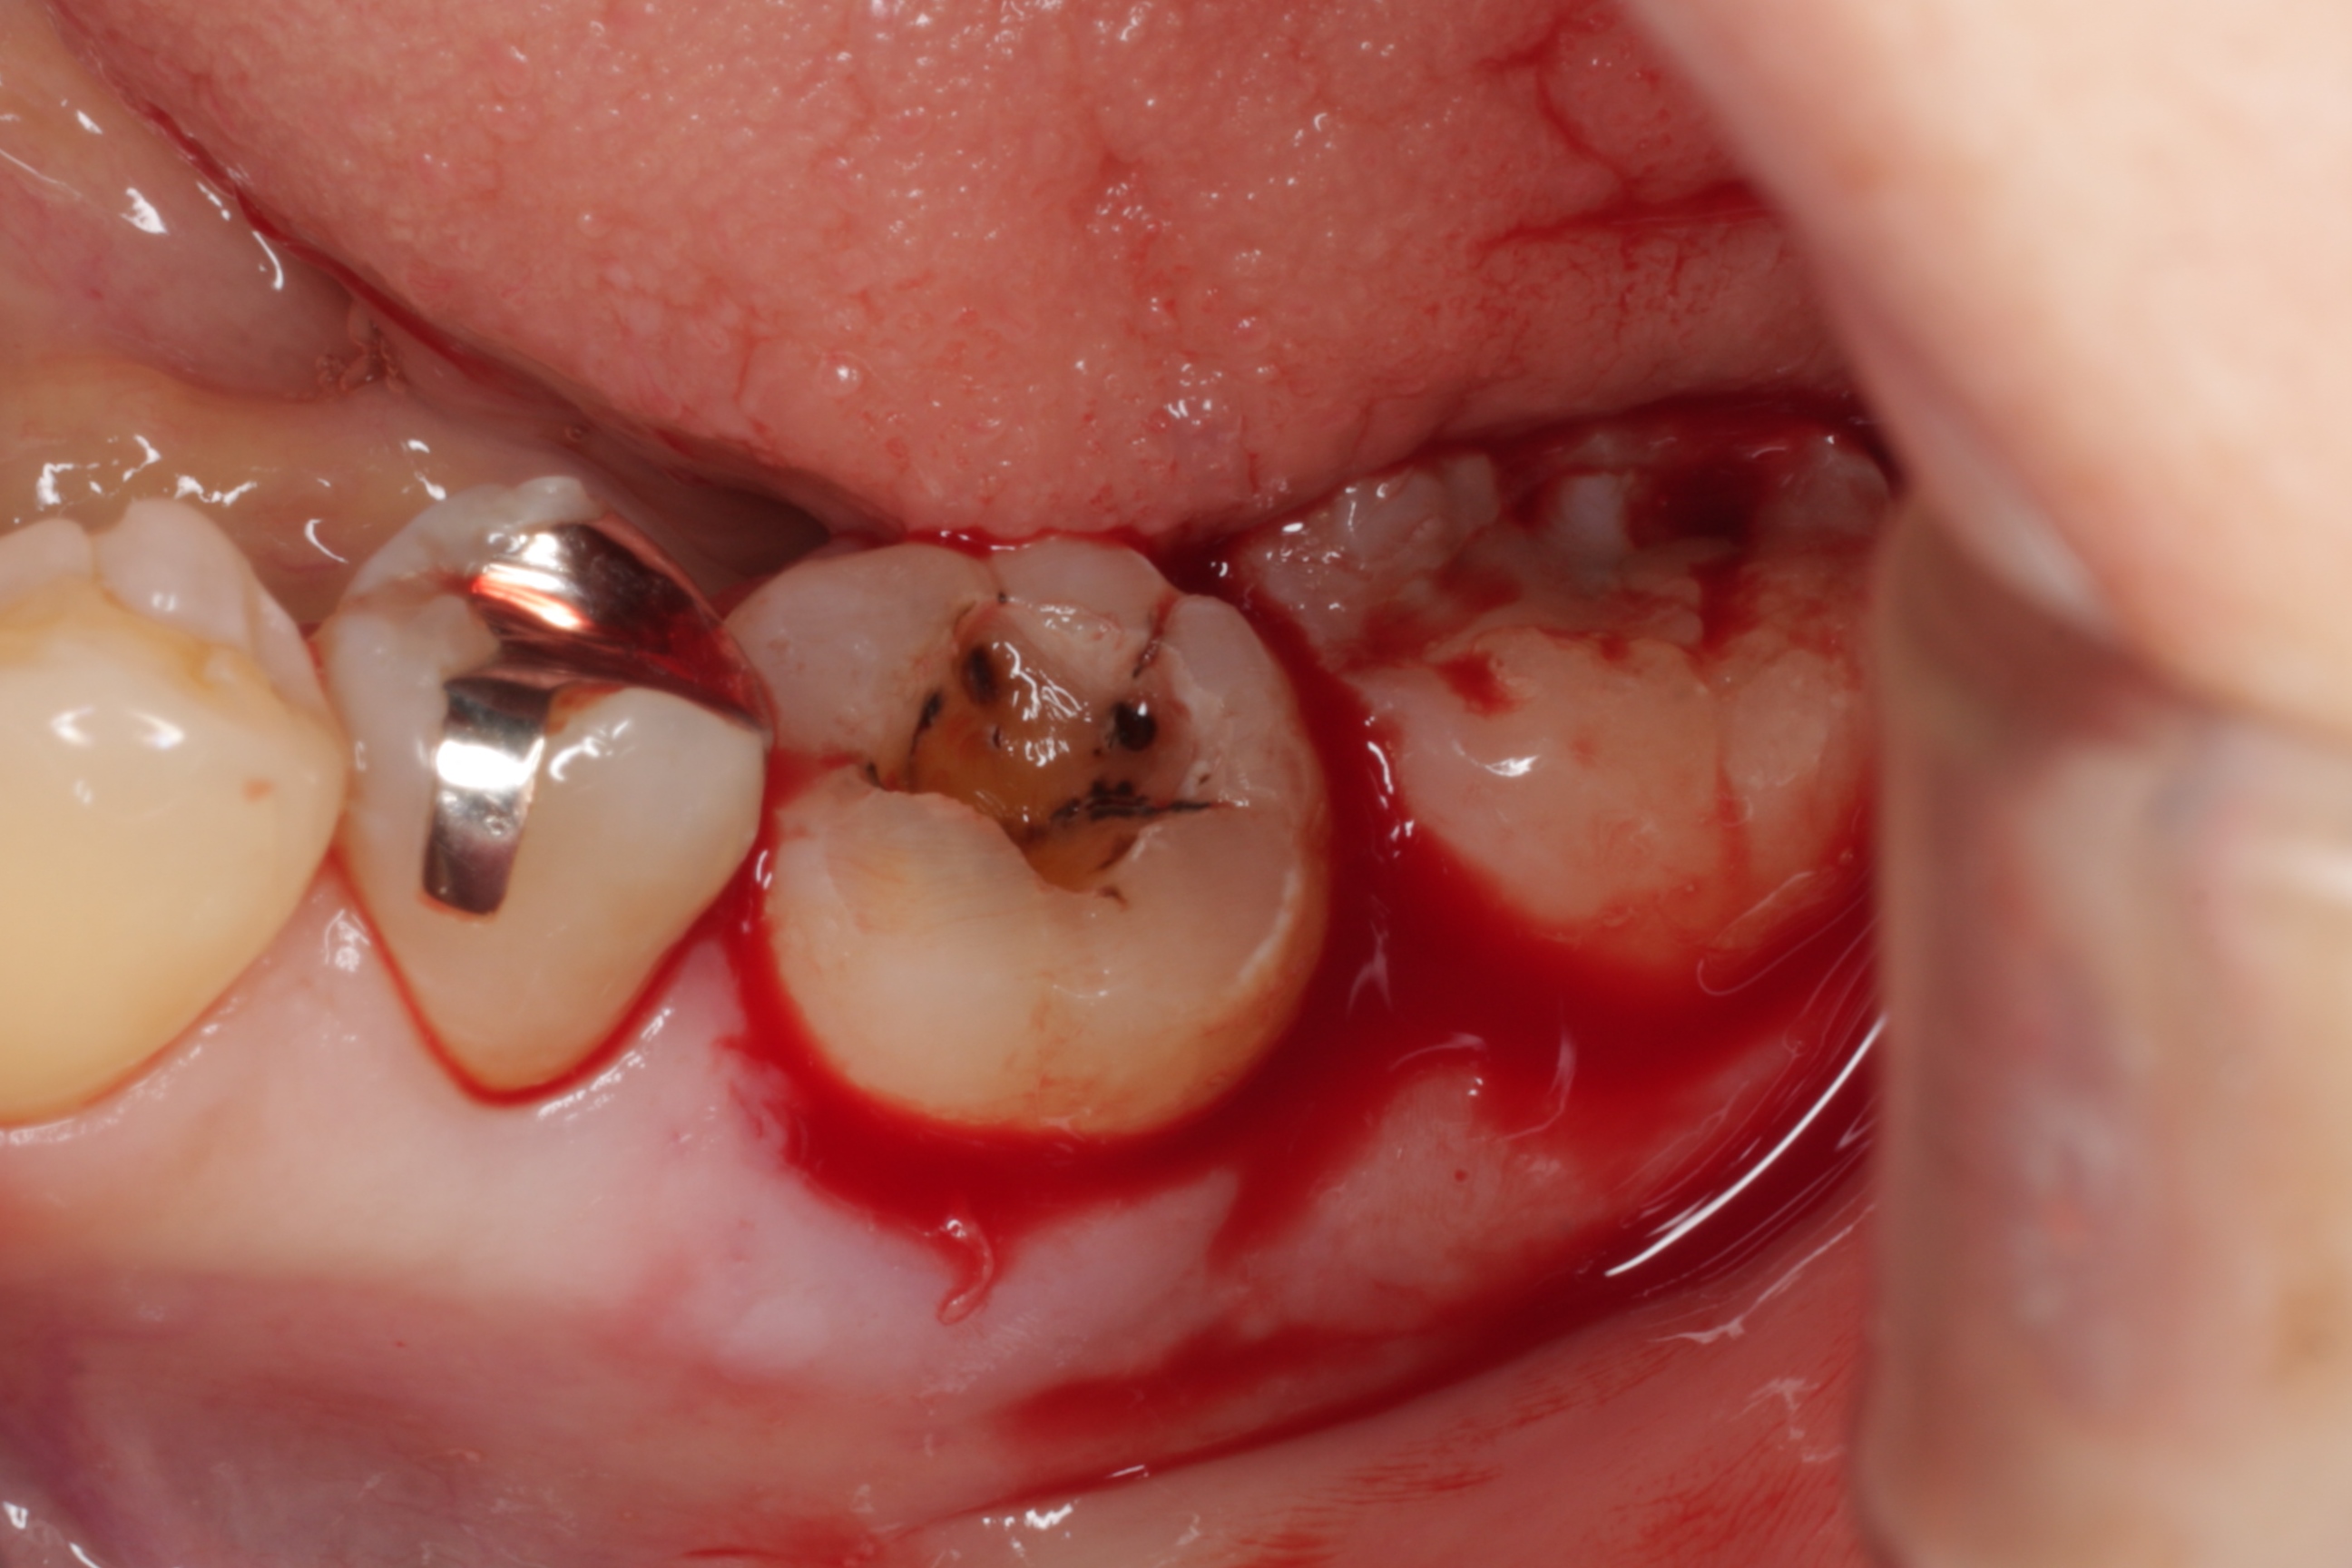

神経を取って、銀歯を被せていた6歳臼歯が割れてしまい、抜くしか方法がなかった患者さんの症例です。

3年前に割れてしまった歯を抜いて、すぐに親知らずを移植しました。